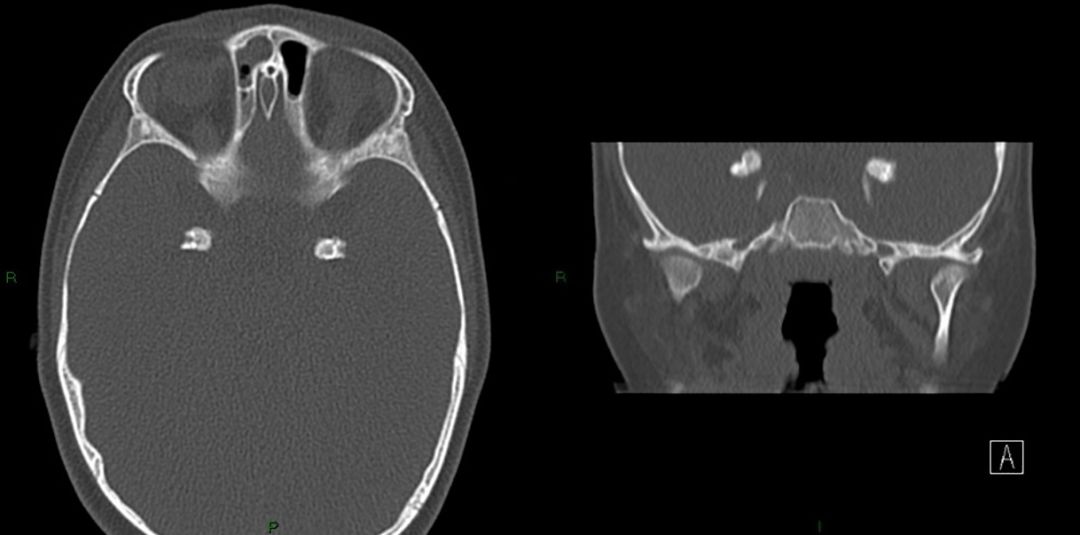

又称小头、纹状体小脑钙化和白质营养不良综合征/侏儒症/视网膜萎缩和耳聋综合征。病理表现为脑白质脱髓鞘外,皮质、基底节及小脑有铁和钙质沉积。常于20—30岁死亡。CT检查除了脑白质脱髓鞘、双侧基底节及其他部位钙化外,可见颅骨和脑膜增厚,脑室和脑沟扩大。

4. 神经纤维瘤病

神经纤维瘤病患者大脑半球及小脑半球表面也可钙化,少数情况下钙化发生在室管膜下及基底节。下图是一例NF-2患者的头CT。